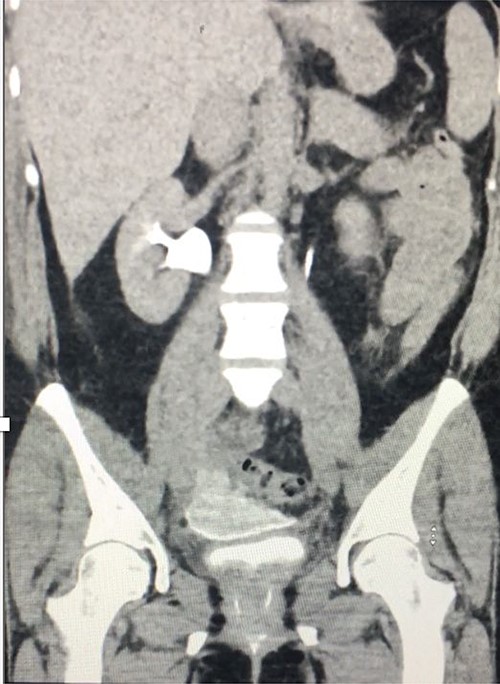

Computed tomography (CT) with urographic phase imaging demonstrated a right distal ureteric injury with leakage of urine into the pelvis and fistulation into the vagina (Figs 1 and 2). A diverting right percutaneous nephrostomy was inserted in the interventional radiology (IR) suite. An antegrade ureterogram at the same time demonstrated a complete discontinuation of the ureter which appeared retracted (Fig. 3).

Coronal delayed phase CT urogram showing pooling of contrast in the pelvis.